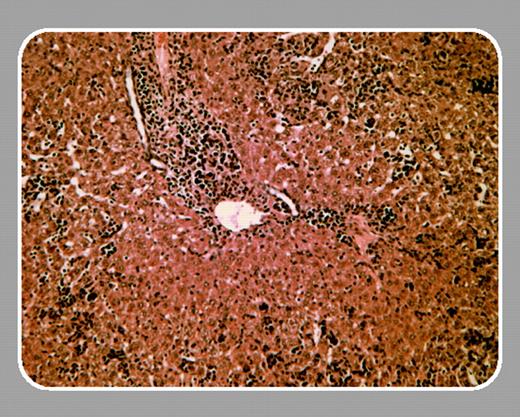

Fascinating insight into the role of phospolipid phosphatases in hematopoiesis has been gained by analyzing knockout mice. Targeted disruption of SHIP results in a myeloproliferative syndrome characterized by splenomegaly and extramedullary hematopoiesis.3 Granulocyte-macrophage progenitor cells are expanded and hypersensitive to growth factors. Pten-/- mice are embryonic lethal. Heterozygous Pten+/- mice survive but frequently develop cancer of different organs, consistent with the known function of Pten as a tumor suppressor.4 The hematopoietic phenotype of these mice is characterized by a progressive lymphoproliferative disease. In this issue of Blood, Moody and colleagues (page 4503) describe the complex hematopoietic phenotype of Pten+/- SHIP-/- mice. The aim of combining haploinsufficiency for Pten with SHIP deficiency was to exaggerate PIP3 dysregulation, potentially leading to leukemogenesis. Surprisingly, Pten+/- SHIP-/- mice did not develop myeloproliferation but did develop a myelodysplasia-like syndrome, characterized by marked leukocytosis, anemia, and thrombocytopenia that was not observed in SHIP knockout mice. Correspondingly, erythroid, megakaryocytic, and primitive myeloid (GEMM) progenitor numbers in bone marrow were markedly reduced. In some aspects, Pten heterozygosity did further aggravate the SHIP-/- phenotype: Pten+/- SHIP-/- hematopoietic progenitors were hyperresponsive to growth factors, and Pten+/- SHIP-/- mice demonstrated an even more pronounced extramedullary hematopoiesis compared with SHIP knockout mice. Interestingly, however, leukemic transformation could not be observed during the limited lifespan of the mice.FIG1